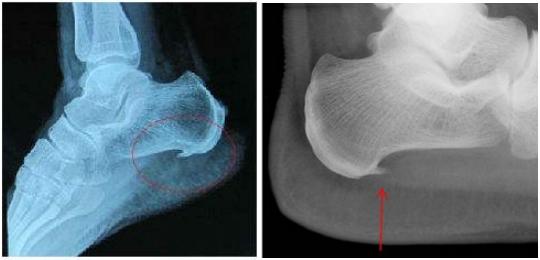

为什么脚后跟会长骨刺?

"骨刺"也叫骨质增生、骨赘。它是人体为弥补衰老磨损、不堪重负的关节而主动、代偿性增生的骨质。它能起到辅助固定、支撑的作用。常出现在骨质流失较为严重的老年人、更年期后妇女身上。

当然,不好好长的骨刺的确会导致脚后跟疼痛。